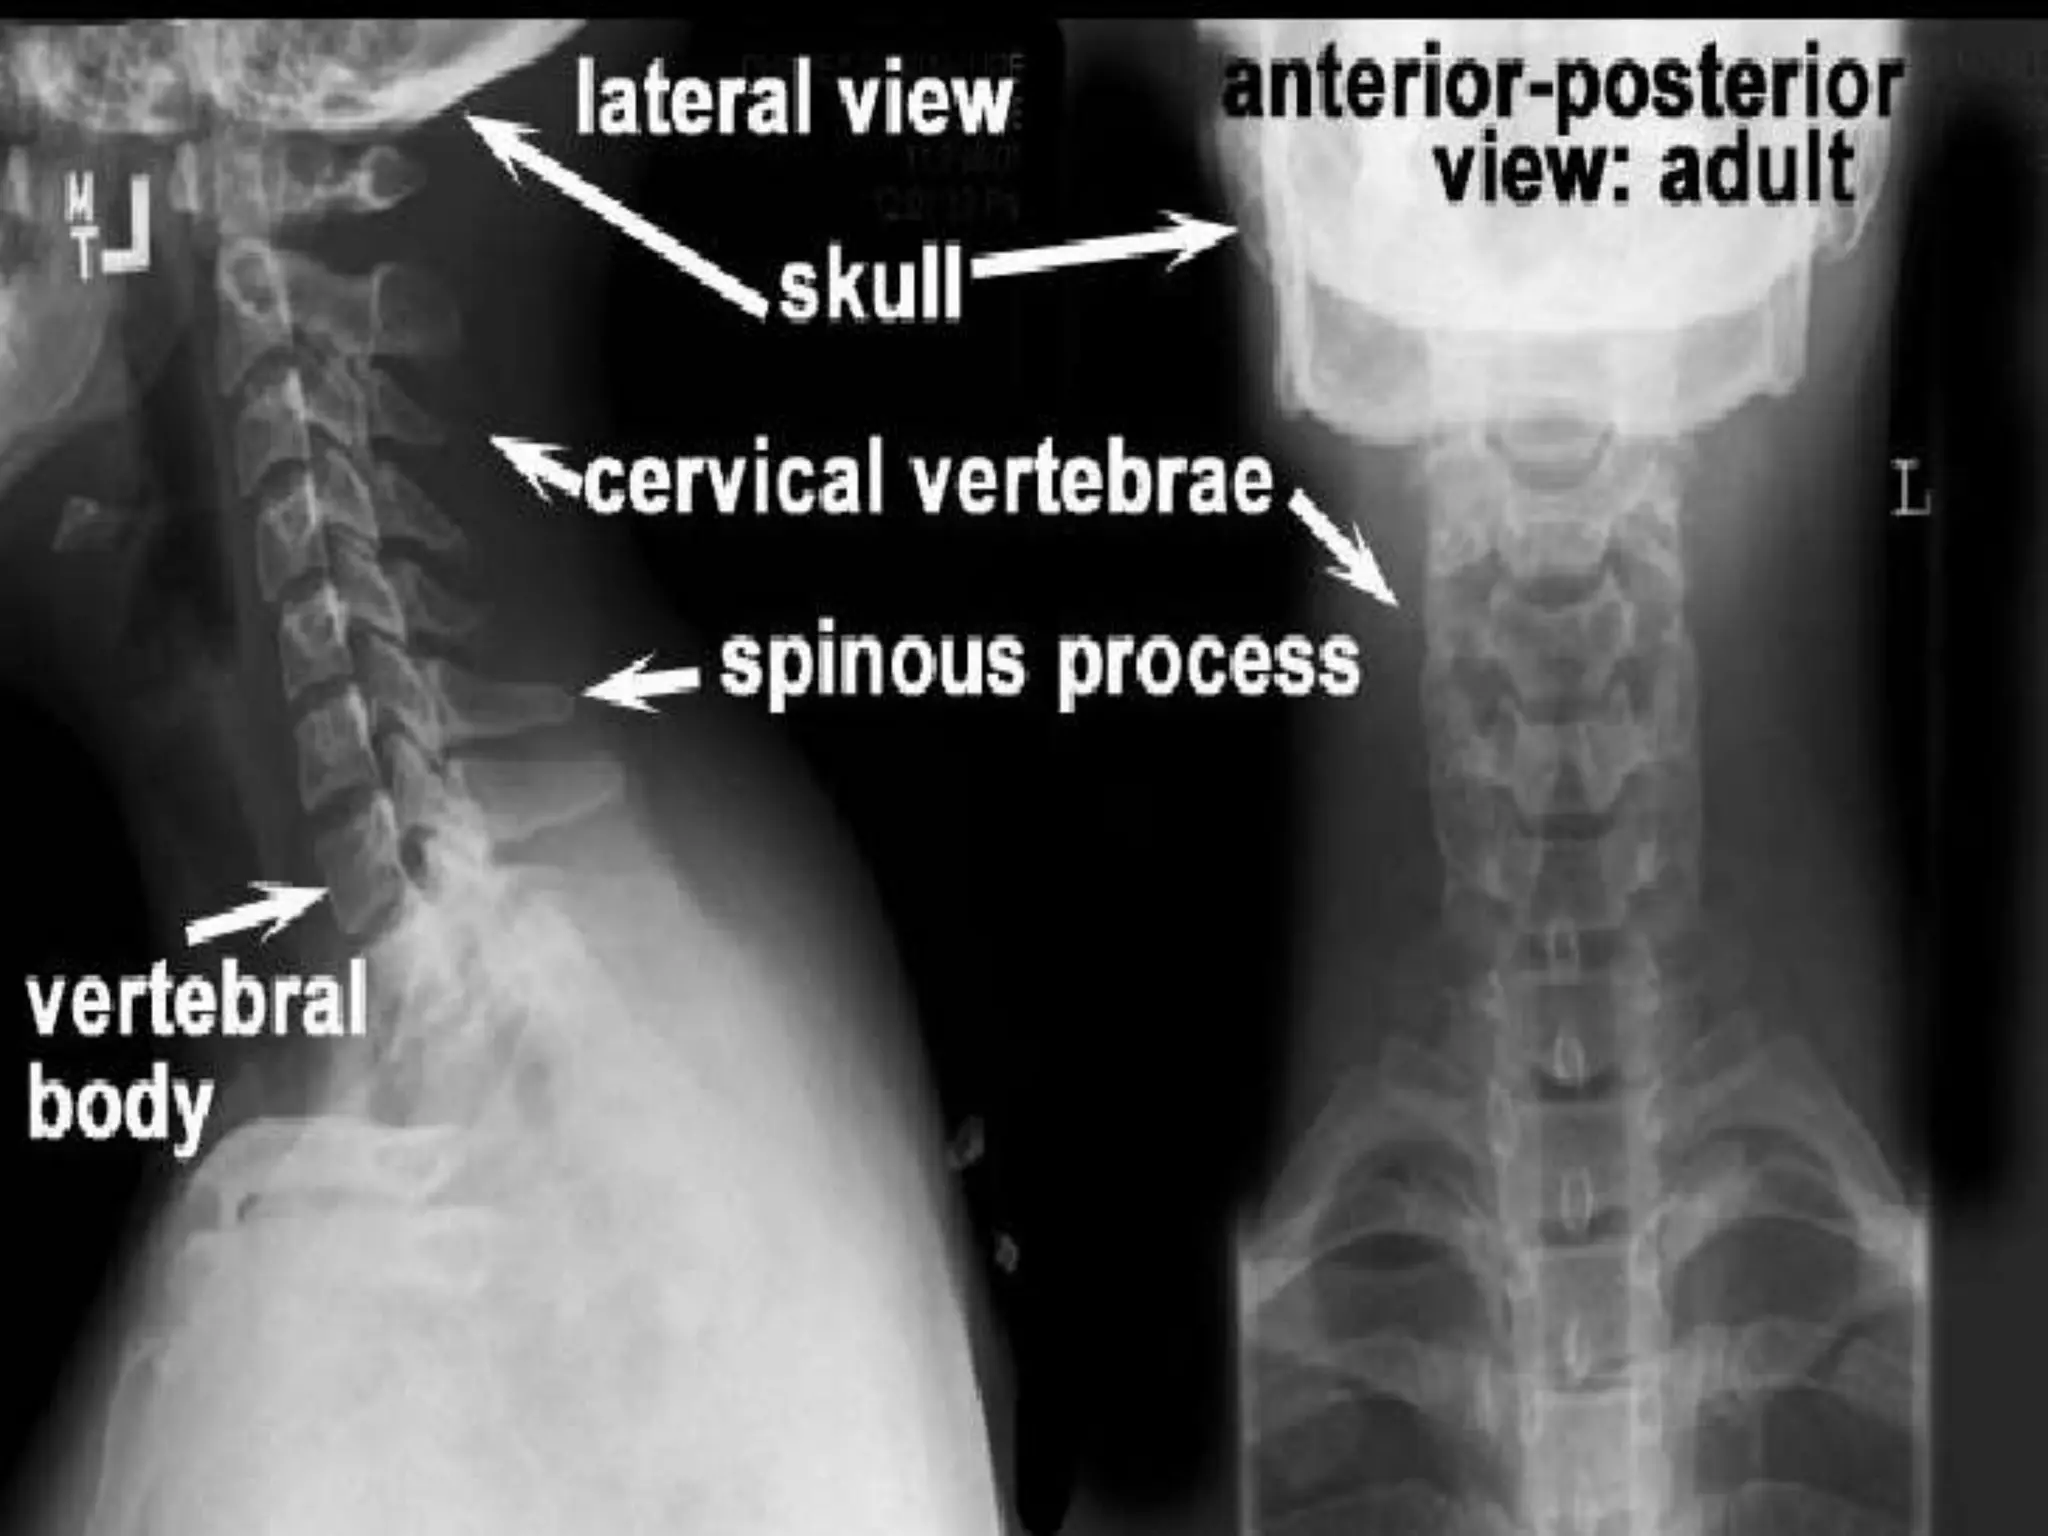

Normal AP and Lateral Views.